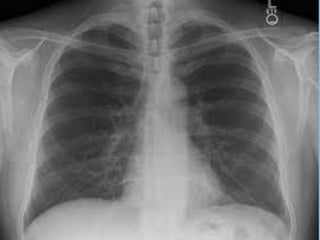

• Diagnosis is imprecise and usually

based on a Combination of:

– CXR factors - new or changing infiltrates

• VAP isa Nosocomial Pneumonia = Hospital acquired • Diagnosis is imprecise and usually based on a Combination of: – Clinical factors - fever or hypothermia; change in secretions; cough; apnea/bradycardia; tachypnea – Microbiological factors - positive cultures of blood/sputum/tracheal aspirate/pleural fluids – CXR factors - new or changing infiltrates